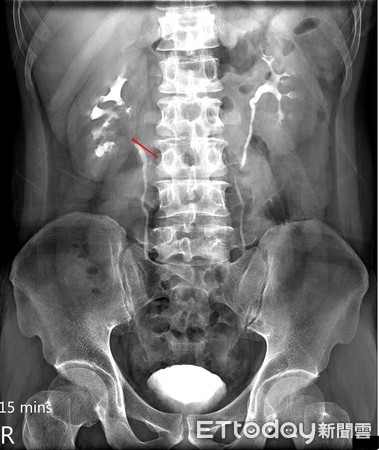

▲患者透過微創手術取出整段輸尿管及膀胱袖口。(圖/亞洲大學附設醫院提供)

蕭子玄表示,患者到院後,經靜脈注射腎盂造影發現右側腎盂疑有腫瘤,於是經過輸尿管鏡切片化驗,確診為「泌尿上皮癌」。醫師透過「腹腔鏡腎臟輸尿管全切除手術」,經由右上腹的幾個小洞,將腹腔鏡鏡頭伸入進行腎臟切除手術,再於下腹部劃一個約7公分的傷口,取出整段輸尿管及膀胱袖口,不僅縮短手術時間及降低手術風險,且傷口較小、流血量少、復原速度較傳統手術快。